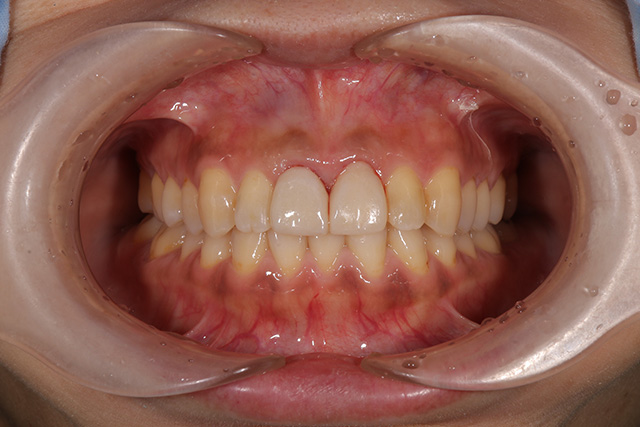

審美症例